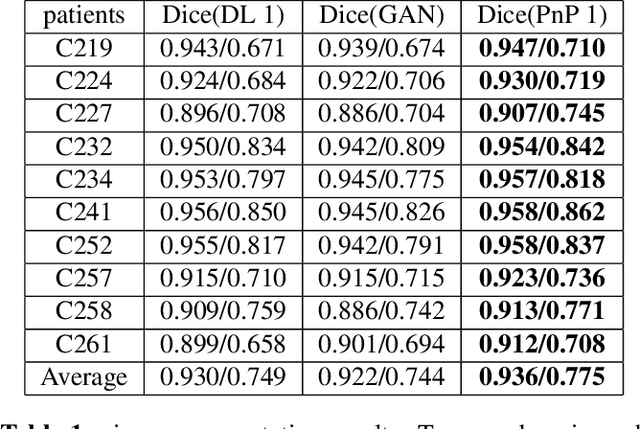

The Plug-and-Play (PnP) framework was recently introduced for low-dose CT reconstruction to leverage the interpretability and the flexibility of model-based methods to incorporate various plugins, such as trained deep learning (DL) neural networks. However, the benefits of PnP vs. state-of-the-art DL methods have not been clearly demonstrated. In this work, we proposed an improved PnP framework to address the previous limitations and develop clinical-relevant segmentation metrics for quantitative result assessment. Compared with the DL alone methods, our proposed PnP framework was slightly inferior in MSE and PSNR. However, the power spectrum of the resulting images better matched that of full-dose images than that of DL denoised images. The resulting images supported higher accuracy in airway segmentation than DL denoised images for all the ten patients in the test set, more substantially on the airways with a cross-section smaller than 0.61cm$^2$, and outperformed the DL denoised images for 45 out of 50 lung lobes in lobar segmentation. Our PnP method proved to be significantly better at preserving the image texture, which translated to task-specific benefits in automated structure segmentation and detection.